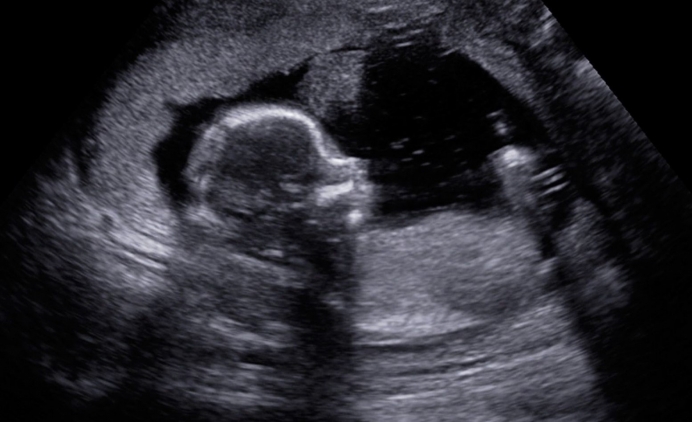

Tweet This: I found the APR hotline number; this morning I had an ultrasound, and my little peanut is alive and well with a strong heartbeat.